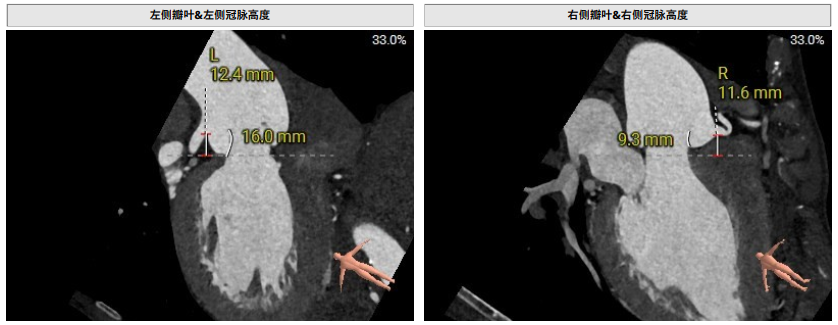

术前影像评估提示,患者主动脉瓣为三叶瓣,分布较均匀,无明显钙化。主动脉瓣环直径约25.5mm,左室流出道直径27.7mm,STJ直径49.9mm,升主动脉直径45.4 mm,冠脉开口高度充足(左冠12.4mm,右冠11.6mm),梗阻风险低。入路角度方面,左室-主动脉夹角为150°,心脏角度60°。

术前评估

手术过程顺利。术中通过右窦居中造影、定位件入窦造影及释放后功能确认等关键步骤,确保瓣膜锚定准确。器械用时仅10分钟。术后患者主动脉瓣重度反流纠正,无反流、无瓣周漏。心脏彩超显示人工生物瓣启闭良好,平均跨瓣压差4mmHg,流速正常。患者恢复情况良好,心脏功能得到显著改善。